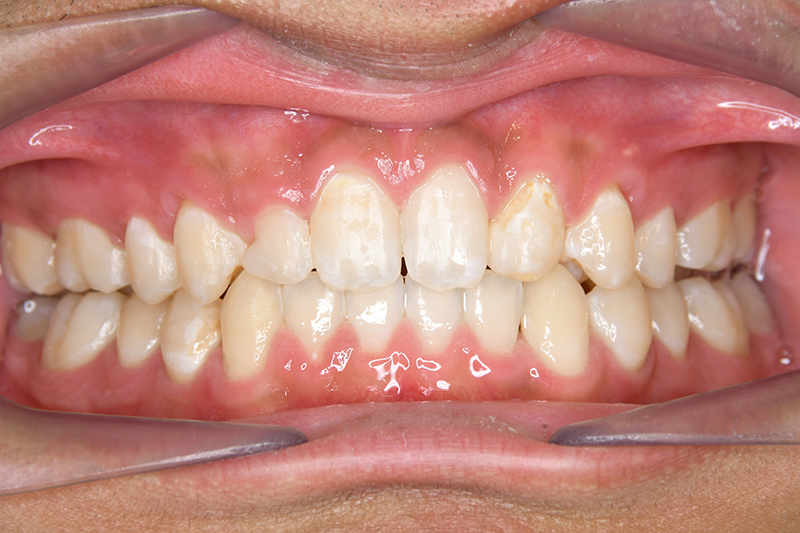

初診時

FP・IOP

主訴 すきっ歯 診断名 上顎右側犬歯先天欠如を伴うアングルⅡ級空隙歯列症例

口腔内所見 over jet 8.0mm、over bite 8.0mmで下顎歯列はスピー湾曲が強く、過蓋咬合、上突歯列、叢生歯列を呈しており、臼歯関係はⅡ級、左側7は鋏状咬合となっていた 。上顎両側2は矮小歯で上顎右側Cは晩期残存をしていた。また上顎歯列は空隙歯列を呈していた。

批評・予后 側貌はconcave typeであり、下顎歯列は叢生が少ないこと、右上3欠損、左右上2は矮小歯であることを考慮して右上C、左側2抜歯とした。治療後はアンテリアレシオの調和を図るべく右上2は暫間的修復(CR)にて歯冠幅径を大きくしている。保定終了後には同部位は最終補綴を装着する予定である。